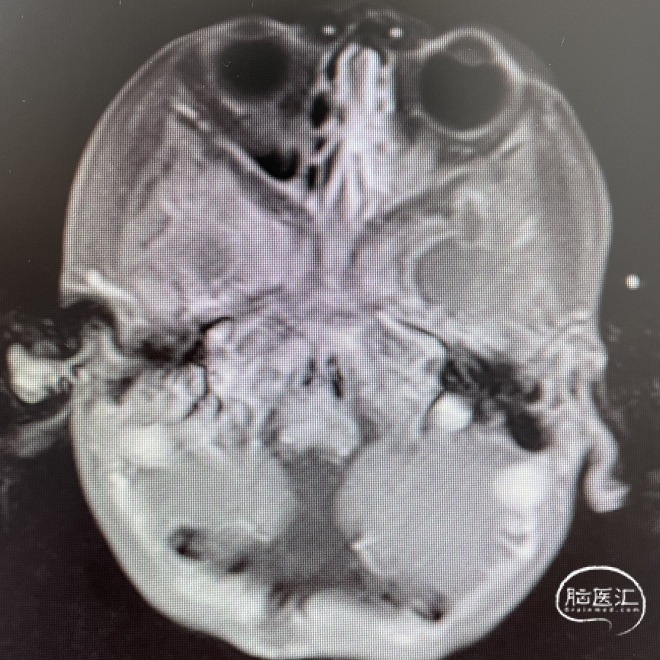

影像学资料

头部MRI检查:第四脑室扩大,其内可见一类圆形肿块,呈稍长T1稍长T2信号,边界清楚,较大截面范围约47*35*48mm。增强后呈不均匀强化;病灶向下延伸至颈段椎管内,向两侧孔延伸至桥小脑角区。幕上脑室系统扩大,周围可见片状长T1长T2信号。

术后